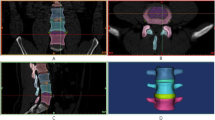

The intact model contained 6 vertebrae, 5 intervertebral discs, and 7 ligaments (Fig. 1A-D). The specific modeling methods referenced previous studies [15,16,17]. 1-mm-thick cortical layers and bony endplates surrounded the cancellous bone. The cartilage endplates with a thickness of 0.5 mm covered the surface of the bony endplates [18]. The nucleus pulposus accounted for approximately 30-40% of the intervertebral disc volume (Fig. 1E). Eight layers of fibers were embedded in the ground substance in concentric rings around the nucleus pulposus (Fig. 1F). The fibers were oriented at an angle of ± 30°-45° from the horizontal surface defined by the bottoms of intervertebral discs. From the outermost (550 MPa) to the innermost (360 MPa) layer, the elastic strength decreased proportionally to ensure the variations in fiber stiffness. According to the anatomical position of ligaments, seven kinds of ligaments were constructed. All ligaments were modeled as tension truss elements. Facet cartilage joints were modeled as frictionless soft contacts. To ensure that the strain energy changes did not exceed 5%, a convergence analysis was performed. The element types and material properties are shown in Table 1.

Finite element modeling of L4/5 TLIF procedures

The TLIF model was built as reported previously in the literature [19]. To simulate the processes of decompression and fusion, a left L4/5 facetectomy was performed; then, the entire nucleus pulposus, the left posterior part of the annulus fibrosus, and capsular and flavum ligaments were removed (Fig. 2A). The central region and the left posterior portion of the cartilage endplate at the L4/5 segment were removed to simulate the endplate preparation. A PEEK cage was placed on the anterior part of the L4/5 intervertebral space (Fig. 2B). Cancellous bone was implanted into the inner and outer spaces of the cage to fill the intervertebral space. The pedicle screw-based fixation system consisted of four screws (diameter, 6.5 mm; length, 45 mm) and two connecting rods (diameter, 5.5 mm; length, 58 mm) (Fig. 2C). The cage-bone graft, cage-endplate, bone graft-endplate, bone-screw, and screw-rod interfaces were assigned a “tie” constraint.